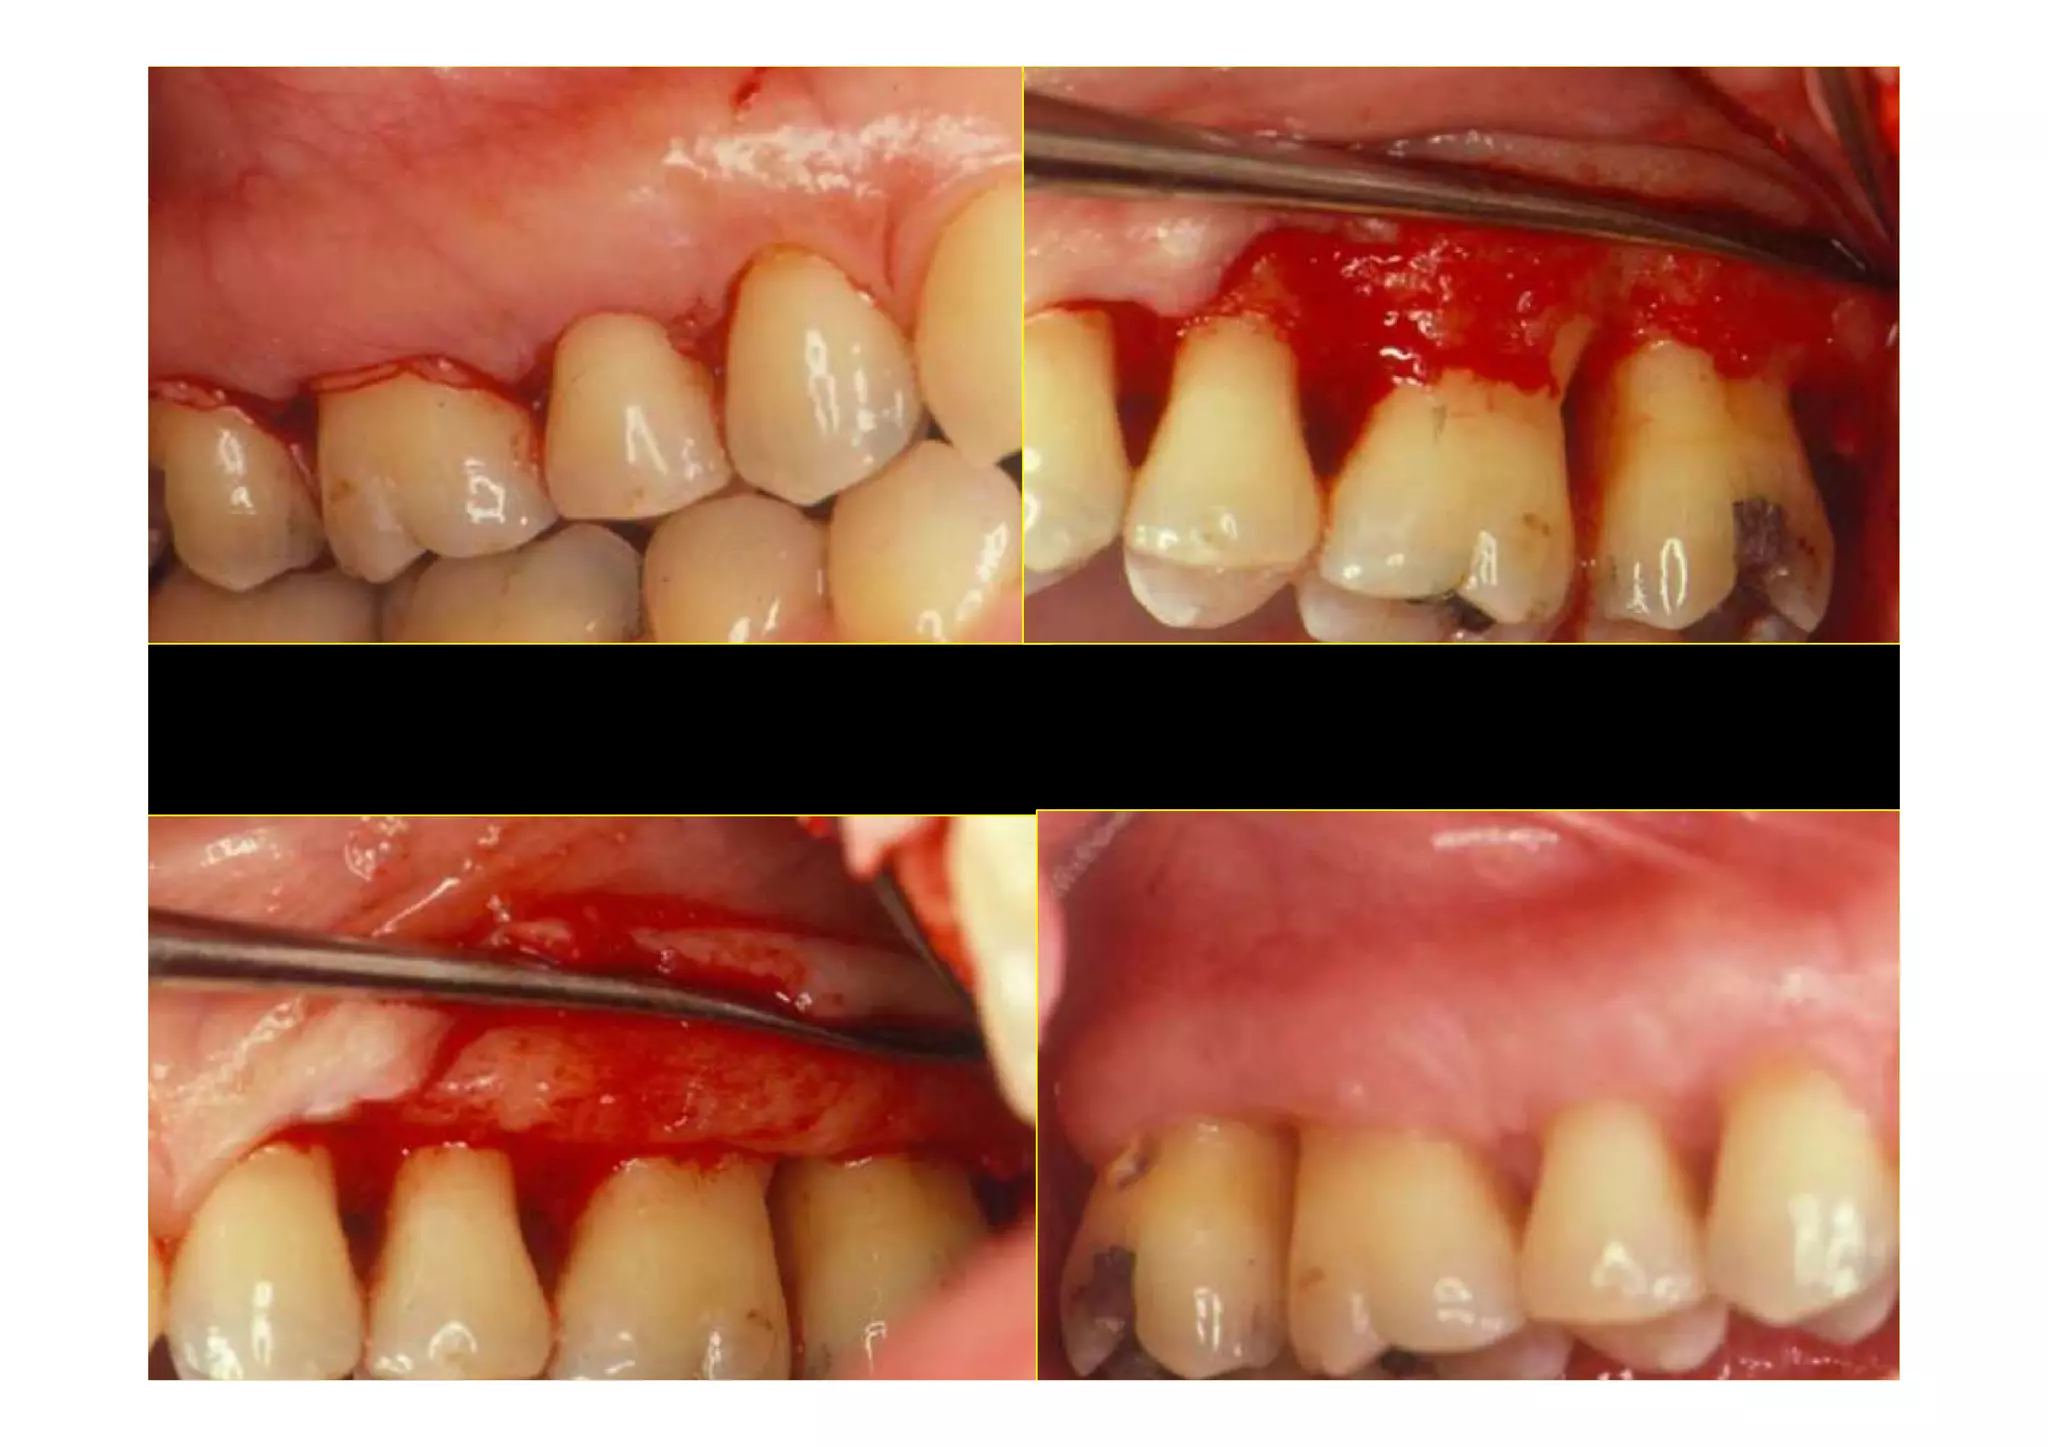

Modified Widman Flap . The main advantage of the modified widman flap surgery over any other periodontal surgical procedure is the intimate postoperative. There are numerous surgical procedures of which modified widman flap is a standard procedure for open debridement.

Modified Widman Flap - Modified widman flap flap debridement surgery is defined: Learn about the origin, evolution and indications of the modified widman flap, a periodontal surgical procedure for pocket elimination. Discover the differences with the original. As surgical debridement of the root surface and the removal of granulation tissue following the reflection of the. The modified widman flap is frequently used as a.

Modified Widman Flap - There are numerous surgical procedures of which modified widman flap is a standard procedure for open debridement. As surgical debridement of the root surface and the removal of granulation tissue following the reflection of the. The main advantage of the modified widman flap surgery over any other periodontal surgical procedure is the intimate postoperative. The modified widman flap is frequently.